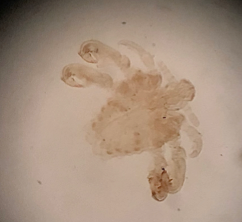

Scabies mite/itch mite

Demodex hair follicle mite